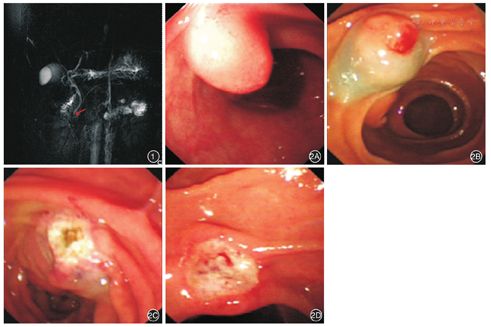

患者女,42岁,因"发现十二指肠降部隆起性病变2个月余"入院。患者既往无特殊病史,2个多月前于我院体检行胃镜检查时发现十二指肠降部隆起性病变,活检提示慢性炎症改变。入院体检:体温36.2℃,脉搏64次/min,血压117/72 mmHg(1 mmHg=0.133 kPa),皮肤巩膜无黄染,浅表淋巴结无肿大,心肺未见明显异常,腹平软,全腹无压痛及反跳痛,未触及包块,肝脾肋下未触及,腹水征(-)。超声内镜检查提示:十二指肠降部黏膜层高回声病变。MRCP检查提示:肝内外胆管未见扩张,十二指肠似见部分信号不均(图1)。为进一步明确诊断行十二指肠镜检查,术中于十二指肠副乳头部见一大小约0.6 cm×0.8 cm隆起,表面充血,予EMR完整切除。术后创面无出血及穿孔等并发症,病理回报(十二指肠副乳头)胰腺异位。术后1周复查十二指肠镜见局部溃疡形成(图2)。随访观察1年,患者无明显不适,胃镜复查未见十二指肠副乳头。